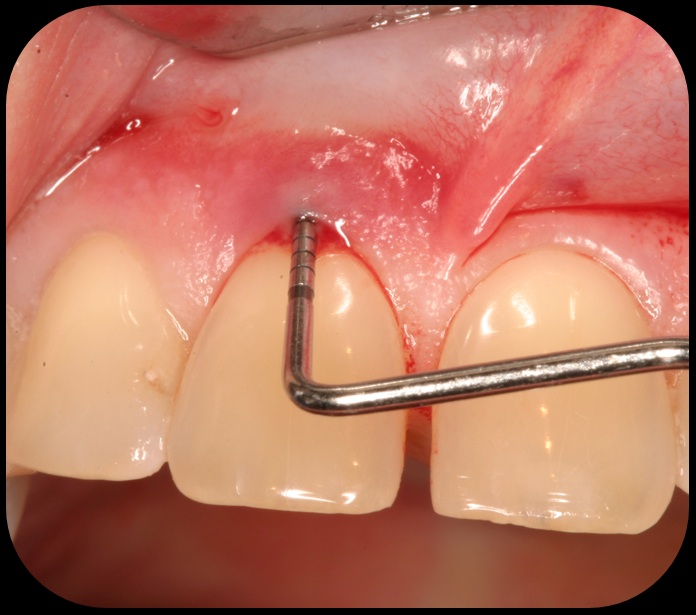

Evidence of clinical attachment gain.

Fig. 6

Then, too, are opportunities to prepare the site for regeneration by coupling therapies, applying an enamel matrix derivative, along with traditional bone grafts of demineralized freeze-dried bone allograft; potentially, gains in attachment with minimal probing depth and retained papilla may avoid the need for an implant (Figure 2 through Figure 7).

In the coming decades, restorative treatment for aging patients who experience facial growth with recession and erosion below the cemento-enamel junction because of tooth movement may be especially challenging. However, if dentists can employ the tenets of regeneration using autogenous tissues or a cellular dermal matrix combined with enamel matrix derivatives as a regulatory protein, they may predictably achieve large amounts of root coverage with thickened periodontium. This would not eliminate the need for restorative dentistry, but would enable restorative dentists to place restorations that are supragingival and are easily accessible for the patient and the therapist during maintenance (Figure 8 through Figure 10).